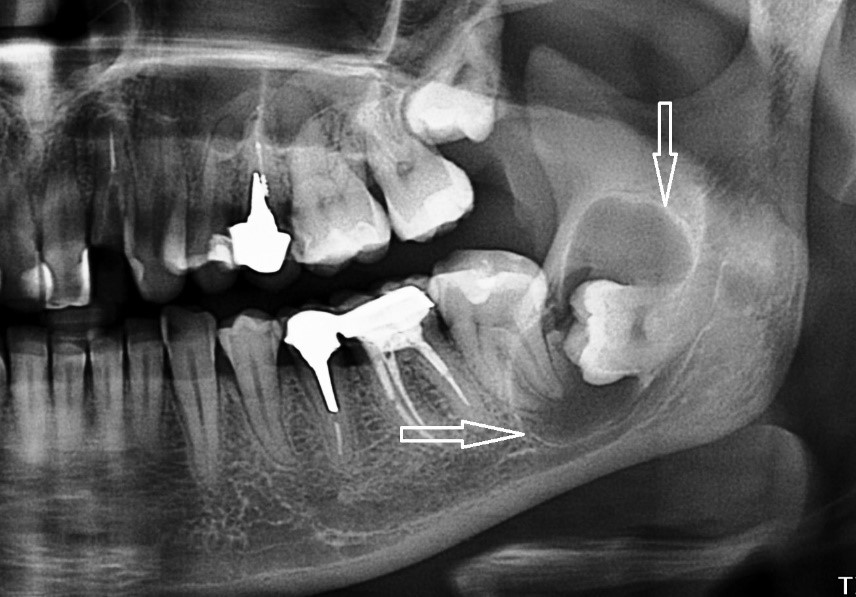

Медицинские Исследования: Кортикальная Пластинка на ОПТГ